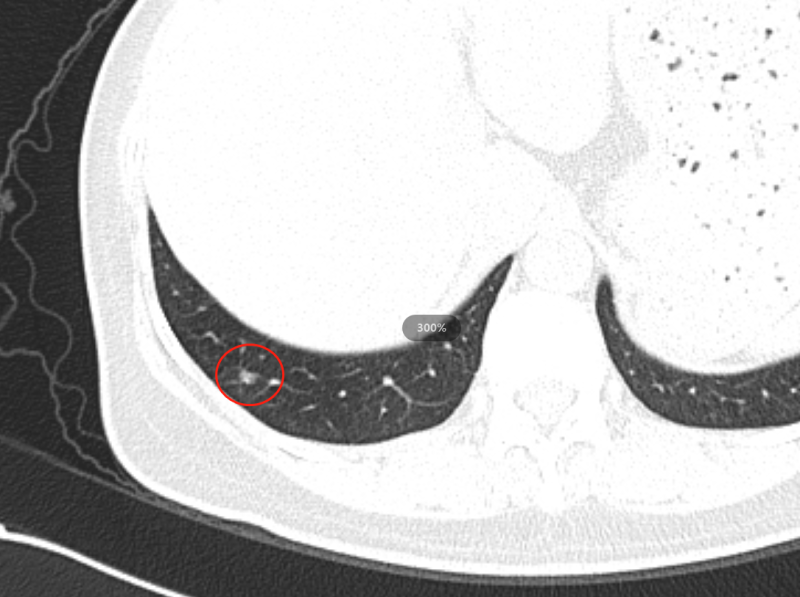

右肺下叶背段纯磨玻璃结节,最大截面约0.9cm×0.9cm,平均CT值约-431Hu,结节呈类圆形,其中可见小空泡,病灶边界清楚,与9年前CT片比较,病灶密度、大小均无明显变化,考虑为微浸润性腺癌-浸润性腺癌,以微浸润性腺癌可能性大。

这个结节诊断还是有难度的↓

结节2

2013年↓

诊断:这个结节是一个混杂密度结节,大部分以实性成分为主,周边可见毛刺及分析,由于病灶非常小,如果首次发现还是要小心,但是通过以下多次的随访和复查,我们考虑良性纤维灶的概率更高。